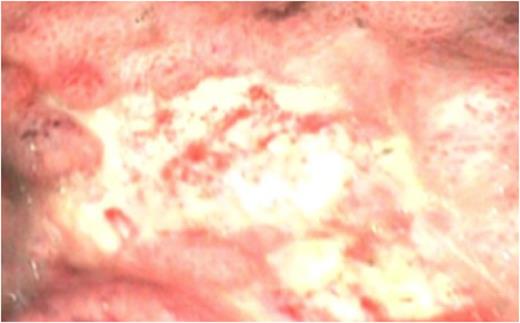

The presumptive diagnosis was of band migration, and an urgent upper G.I. endoscopy was performed. This demonstrated a normal calibre proximal stomach, which narrowed sharply at the mid-body (fig 1.).

OGD showing a normal calibre proximal stomach, which narrowed sharply at the mid-body.